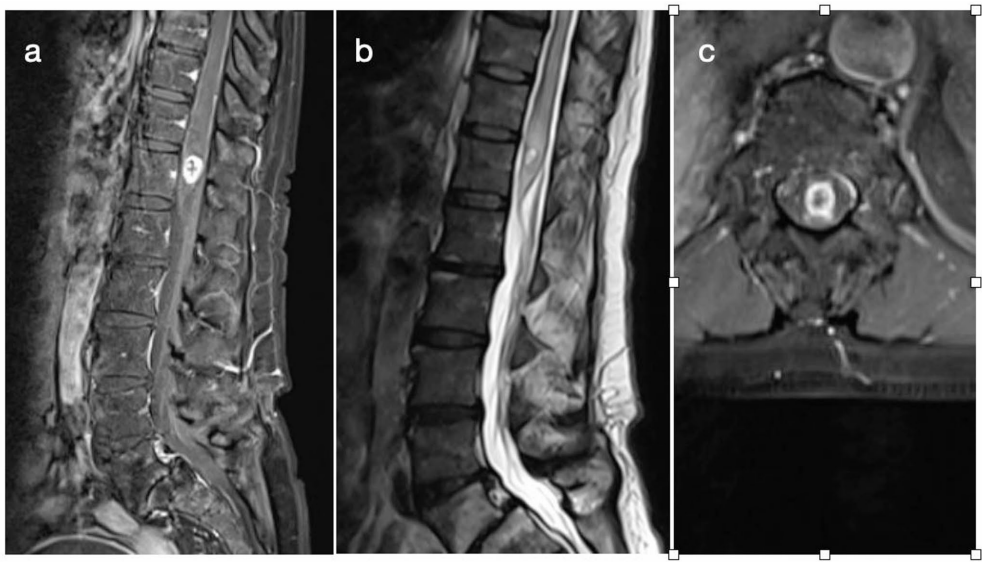

研究团队回顾分析了2015-2024年间16例经病理确诊的ISCM手术病例,创新性地将患者按手术范围分为活检组、部分切除组和全切除组。通过系统评估围手术期并发症、神经功能变化和90天生存率,同时结合30年文献数据,揭示了ISCM治疗的新范式。研究发现,虽然全切除组90天死亡率最低(13% vs 部分切除60%),但多变量分析显示切除范围本身并非独立预后因素。更令人振奋的是,所有患者神经功能均保持稳定或改善,McCormick评分改善率达13%,且无永久性神经损伤发生。这些发现彻底颠覆了"切除越彻底预后越好"的传统认知。

关键技术方法包括:采用术前术后MRI定量评估切除范围(EOR);使用McCormick评分(mMCS)和运动评分(MS)标准化神经功能评估;通过Charlson合并症指数(CCI)量化系统性疾病负担;采用Kaplan-Meier法分析生存影响因素。研究队列来自单中心连续病例,所有手术均在神经电生理监测下由资深团队完成。